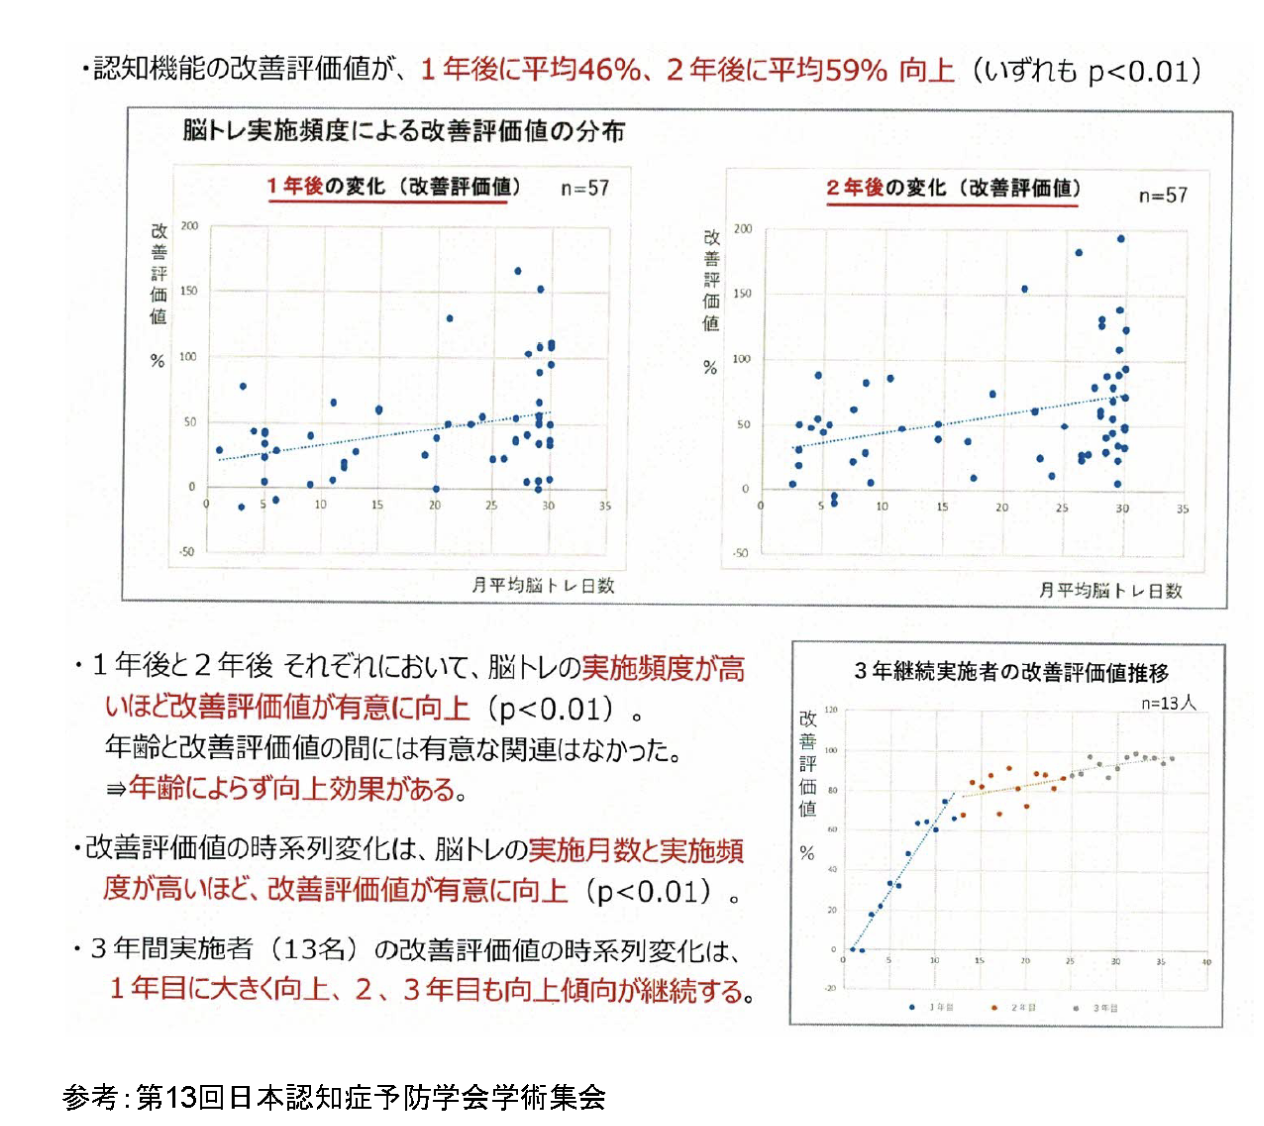

脳トレ継続利用者の認知機能向上効果に関する検証

【症状別・脳の機能区分】